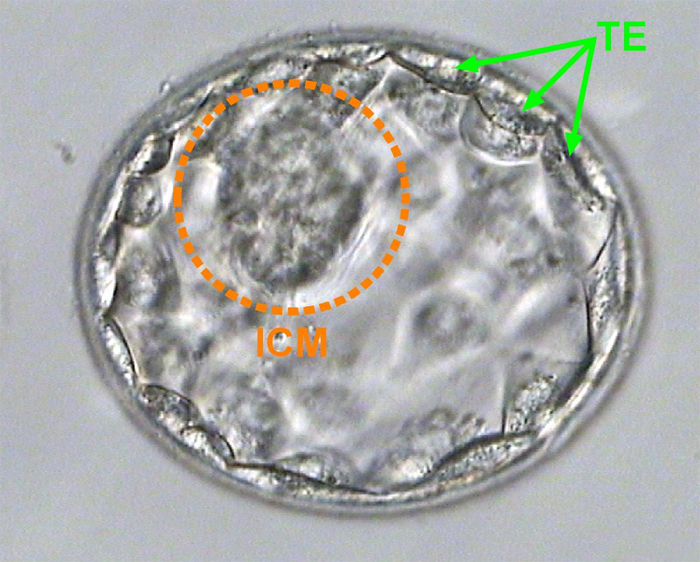

عندما تصل الأجنة لمرحلة اليوم الخامس: تنقسم خلايا الجنين إلى قسمين:

* الخلايا التي تكون الجنين (ICM)

الخلايا التي تكون المشيمة (TE)

* ويتم أخذ عينة صغيرة من الخلايا التي تكون المشيمة بعد أن يتكاثر عدد الخلايا التي تكون الجنين لدرجة كبيرة

لا يؤثر أخذ العينة على الجنين في مرحلة اليوم الخامس أو السادس إطلاقا وهذا ما أكدته الأبحاث الطبية بمالا يسمح للشك، وذلك لأن العينة لا تؤخذ من الخلايا التي تكون الجنين (مشار إليها ب ICM بالرسم) بل الخلايا التي تكون المشيمة (مشار إليها TE بالرسم). وهذا بخلاف أخذ العينة من جنين اليوم الثالث والذي أكدت الأبحاث أنه يؤثر على الجنين بصورة سلبية.